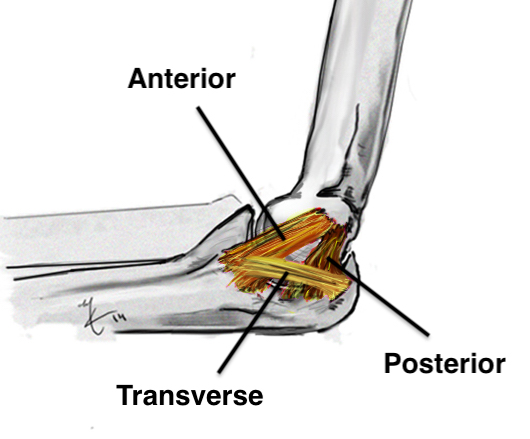

Anatomy of Ulna Collateral Ligament (UCL)

Provides valgus stability

Three components

| Anterior band | Posterior band | Transverse band |

|---|---|---|

|

Most important Stabilizes from 30 - 90 degrees flexion |

Fan shaped Stabilizes from 90 - 120 degrees |

Does not cross elbow joint Does not contribute to vaglus stability |

| Medial epicondyle to sublime tubercle |

Medial epicondyle to medial semilunar notch of ulna |

Medial olecranon to medial coronoid |

|

Taut band Mean 6 mm thick |

||

|

|

|